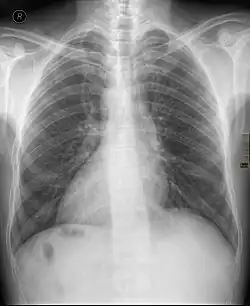

| Chest X ray of a person with dextrocardia situs inversus showing the cardiac apex pointing towards right | |

Dextrocardia situs inversus refers to the heart being a mirror image situated on the right side. For all visceral organs to be mirrored, the correct term is dextrocardia situs inversus totalis.[5][6]